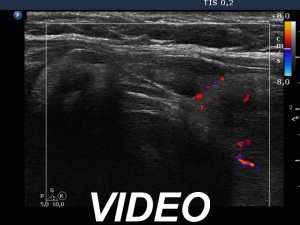

Second examination 3 years later (second, fourth and sixth rows of images):

Clinical presentation: The patient requested a repeat examination because she has had already neck discomfort and occasionally difficulties in swallowing. She first noticed these complaints 3 months ago. She was under regular oncology check-up and was last checked for 2 months. At the time, it was still not considered warranted to treat lymphoma.

Palpation: Both thyroid lobes were enlarged and firm lesions were palpable in both lobes.

Laboratory tests: TSH 1.98 mIU/L, anti-TPO 4.1 U/mL, ahTg 527 U/mL.

Ultrasonography. Compared with the previous examination, both the number and the size of discrete lesions in the thyroid have increased.

Suggestion: Repeat oncological check-up.